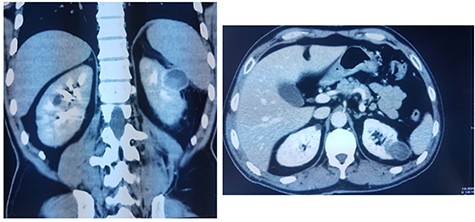

This is a 50-year-old patient with a history of medically treated renal lithiasis, who consults for left low back pain. The patient was apyretic and reported no urinary symptoms. The clinical examination was without any particularities. There was no organomegaly or lumbar contact on bimanual palpation. Biologically, there were no abnormalities, including no biological inflammatory syndrome, and renal function was preserved. The urine culture was sterile. Renal ultrasound revealed a 3-cm left cortical renal mass with moderate vascuarization. Abdominal CT scan confirmed the presence of a heterogeneous Bosniak type 3 cystic mass having a thickened wall (Fig. 1). Abdominal MRI showed a left polar cyst having an exophytic development and a thickened wall with spontaneous T2 hypointensity and T1 hyperintensity without any pathological enhancement after Gadolinium injection (Fig. 2). The retained diagnosis was an hemorrhagic benign cyst. At multidisciplinary meeting, the decision was to perform an MRI 3 months later which showed a left medio-renal cortical cystic mass measuring 24 × 28 mm having a T1 hyperintensity and heterogeneous T2 hypointensity, with a thickened wall mildly enhanced after contrast injection evoking a Bosniak type-3 hemorrhagic cyst. Seeing the MRI results, we decided to perform a left tumorectomy. Pre-operatively, the perirenal tissues were inflammatory and adherent to the capsule, a complete dissection of the kidney was performed allowing the identification of the tumor which was of a 3-cm diameter and a partially exophyctic development, then we cut the tumor with a 2-mm surgical margin. No urinary tract leakage was observed. Finally, renorraphy was performed in two plans using Vicryl 2-0 and 1 (Ethicon, Cincinnati, OH, USA). After confirming the lack of active bleeding, we placed a drainage tube and closed the incision. The total operation time was 1 h 45 min, with 18 min of selective clamping. The post-operative course was uneventful, and the patient was discharged 2 days post-operatively. The histopathological examination revealed a 2.5 × 2.7 cm necrotic lesion with an inflammatory interstitial infiltrate dissociating the epithelial structures (Fig. 3). The retained diagnosis was a pseudo tumoral Xanthogranulomatous pyelonephritis. The CT performed 3-months after surgery showed no abnormalities.

CT showing a heterogeneous Bosniak type-3 cystic mass having a thickened wall.